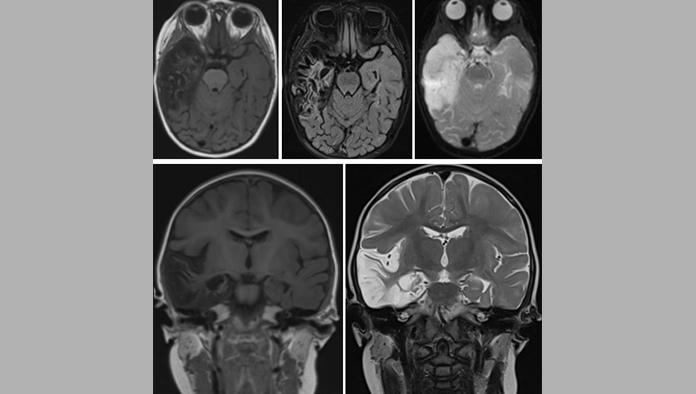

La encefalitis es una enfermedad que comporta una inflamación del sistema nervioso central, fundamentalmente del cerebro (encefalitis) pero también puede afectar por proximidad a las meninges (meningoencefalitis) y en la médula espinal (encefalomielitis). Aunque sus causas son variadas, la más frecuente siguen siendo los virus.

Cuadro clínico de la encefalitis

El cuadro clínico característico de la encefalitis consiste en:

-Fiebre

-Alteración del nivel de conciencia.

-Dolor de cabeza

-Crisis epilépticas

Diferentes tipos de déficits neurológicos, dependiendo de las partes del cerebro más afectadas (problemas para hablar, parálisis o alteraciones de la sensibilidad, alteraciones visuales…).